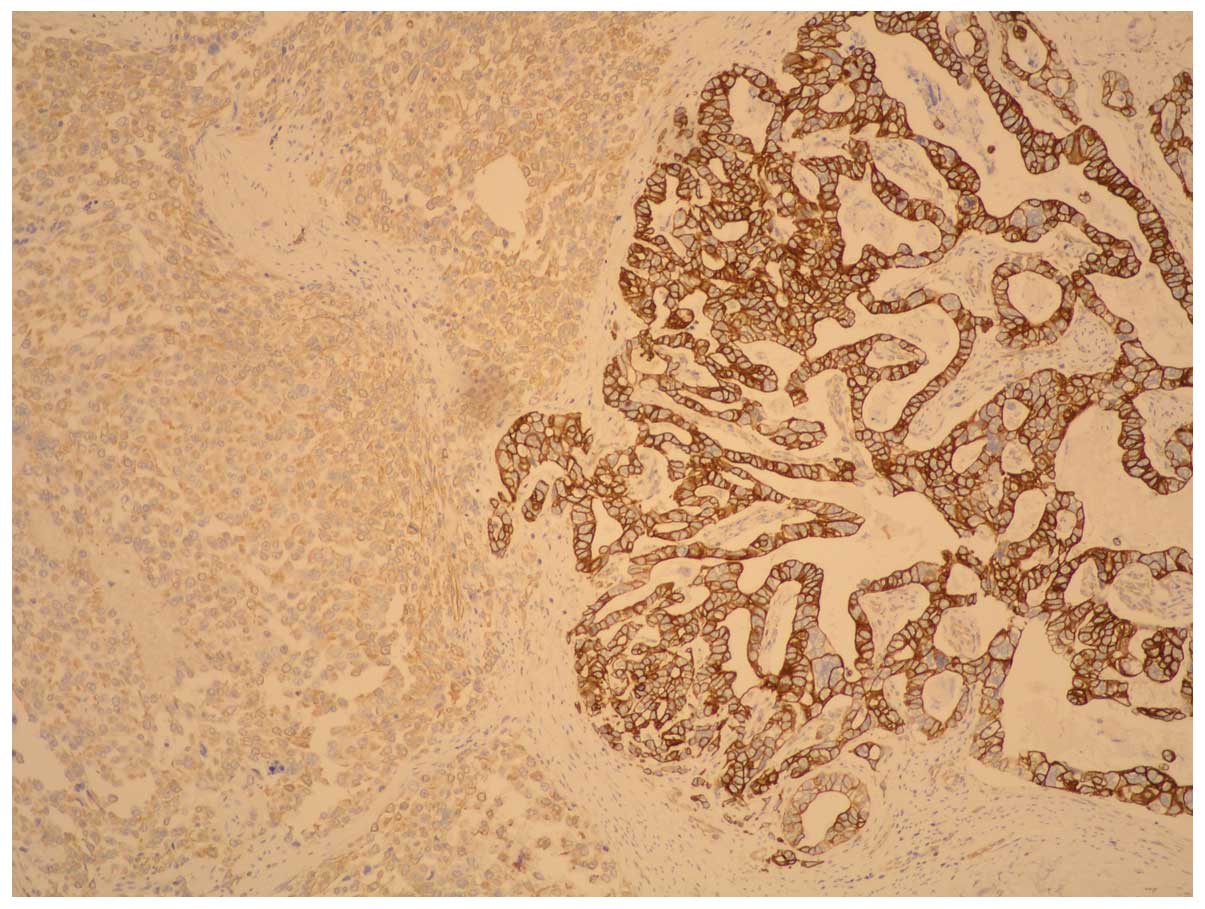

The carcinoma component exhibited a positive

reaction to pan-cytokeratin whereas fusiform cells showed positive

reactions to vimentin: HHF35; CD56; EMA (weak); desmin (singular

component) and negative reactions to cytokeratin, actine,

caldesmon, CD-34, S-100 and cromogranin; synaptophysin, CD-57 and

c-kit. These immunohistochemical findings led to a diagnosis of

gastric carcinosarcoma (Figs. 4 and

5).